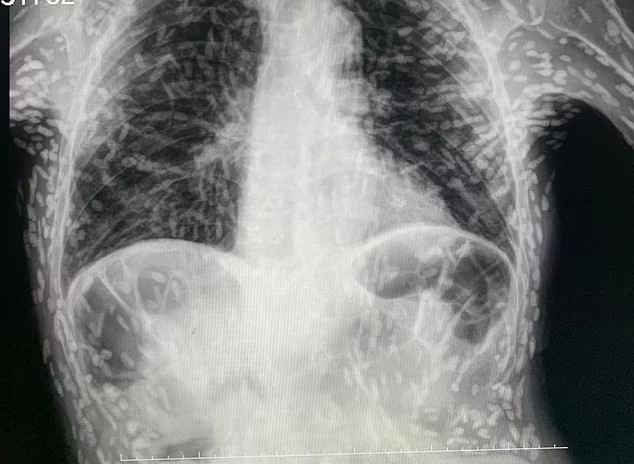

Phim X-quang hé lộ nguyên nhân ít ngờ khiến bệnh nhân ho dai dẳng

Theo Daily Mail, hình ảnh do bác sĩ Vitor Borin de Souza (Bệnh viện Clinicas in Botucatu, Brazil) cung cấp. Trên phim có hàng trăm đốm trắng, mỗi đốm đại diện cho phần bị vôi hóa của một loại ký sinh trùng.

Tình trạng này, được gọi là bệnh nang sán, xảy ra khi ấu trùng của một loài sán dây, thường sống trong ruột, xâm nhập vào các mô như cơ hoặc não. Ở đó, chúng tạo thành các nốt cứng giống như u nang dưới da.

Mặc dù gây khó chịu nhưng các ấu trùng đã chết nên thường vô hại trừ khi tồn tại trong não, dây thần kinh hoặc mắt. Bác sĩ Souza lý giải: “Người bệnh ăn phải trứng sán dây (tồn tại trong chất thải của người bị sán dây). Bởi vậy, bạn phải rửa kỹ thực phẩm trước khi ăn”.